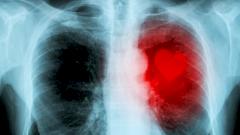

В одну из больниц Подмосковья поступила женщина после эпилептического припадка. Пациентка была без сознания. Обследование выявило причину ее состояния — крупную опухоль головного мозга.